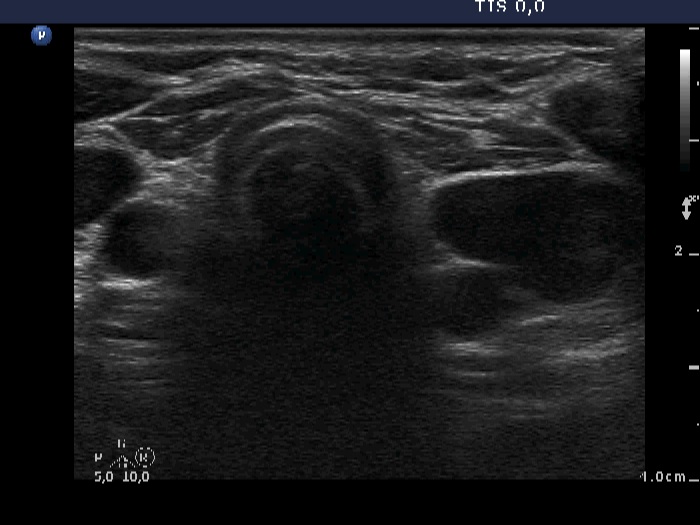

Ultrasonography. There was no parenchyma in the thyroid beds, connective tissue replaced the thyroid. Lateral and upper to the left thyroid bed, multiple moderately hypoechogenic, inhomogeneous nodules were found next to each other. The largest, longitudinal diameter of the mass was 43 mm.